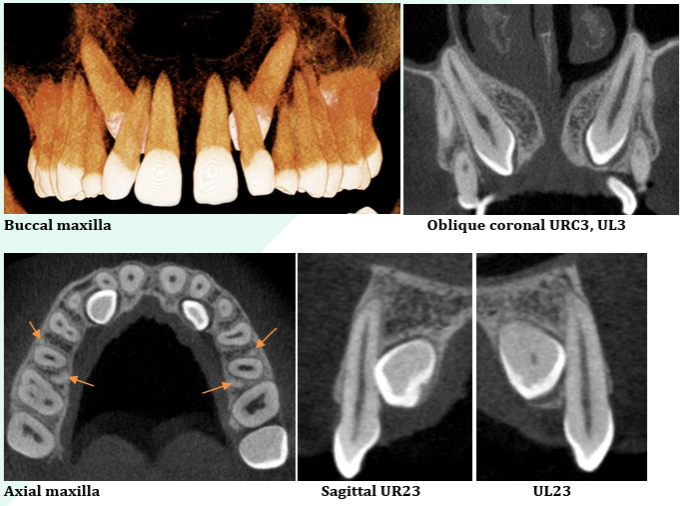

– Precise measurements and high-resolution annotated screenshots

Evaluating for implants

Bone measurements for implant planning

Sinus evaluation

TMJ evaluation

Head and neck reporting

Reporting of CBCT scans done your practice

Find some sample reports in PDF here: